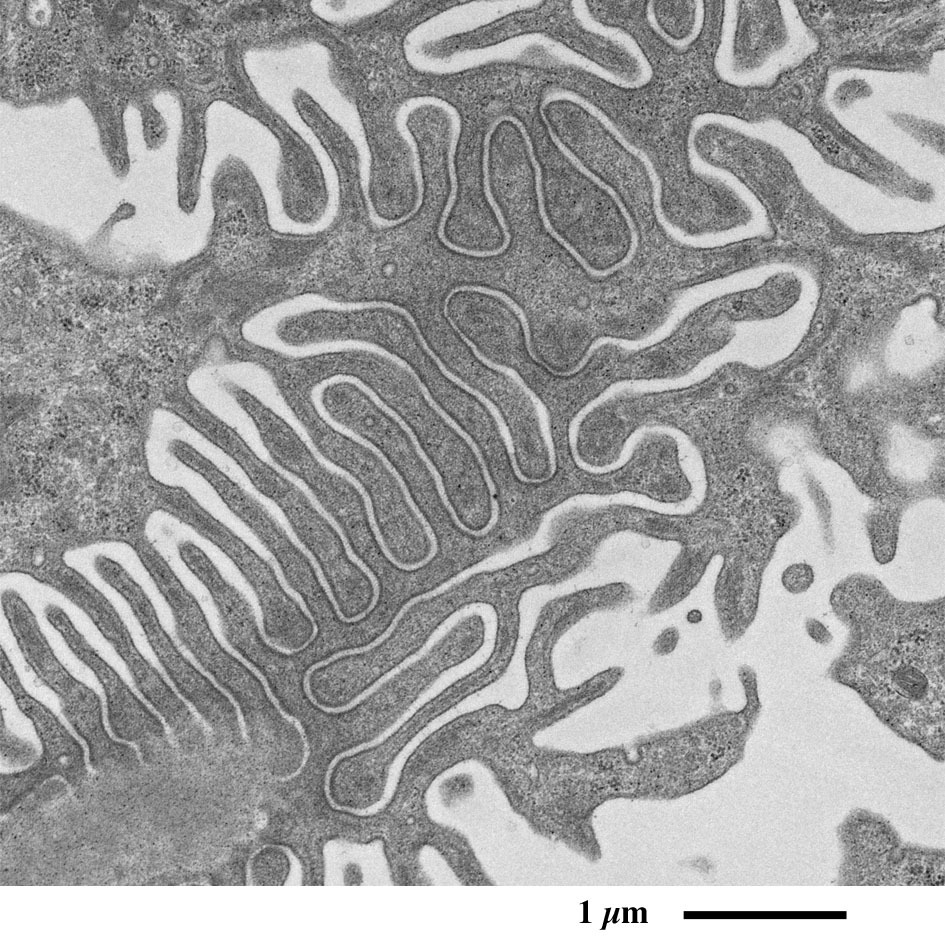

【超薄切片的透射电子显微镜图像】

Transmission electron microscopic image of ultrathin section

肾小球的电子显微镜图像

表面含有足细胞的毛细血管蟠曲穿行于肾小囊腔中,

其外周被肾小囊包裹。

肾小球放大图像

可观察到足突在毛细血管外周包绕的形态。